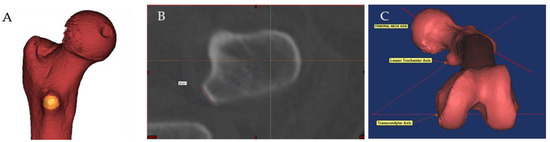

| Lesser trochanter version | 38.54° ± 7.86° | 16.99° to 54.38° | 0.98 | 0.98 |

| Femoral anteversion | 11.84° ± 10.06° | −17.63° to 43.98° | 0.99 | 0.99 |